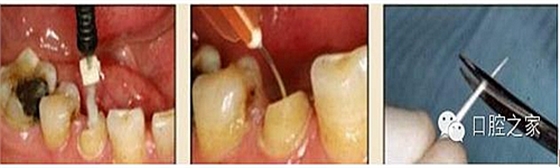

6.纖維樁的試放和裁截

纖維樁試放時應(yīng)選用鑷子夾持將其插入預(yù)備根管,就位時無阻力且稍有匡量(圖 13),禁用污染手套或止血鉗夾持(圖 14)。試放合適后應(yīng)按所需長度用細顆粒金剛砂車針切割裁截。切勿使用技工鉗或粗顆粒金剛砂片(圖 15),以免造成纖維撕裂散開,使纖維樁機械性能降低。由于在裁剪過程中有可能造成樁的表面污染,也可以粘接固位后再進行裁剪。臨床操作時,應(yīng)在樹脂核成型后,頰、舌、合面分別光照20s,在完成預(yù)備體時將其磨除(圖16)。 ##pages##